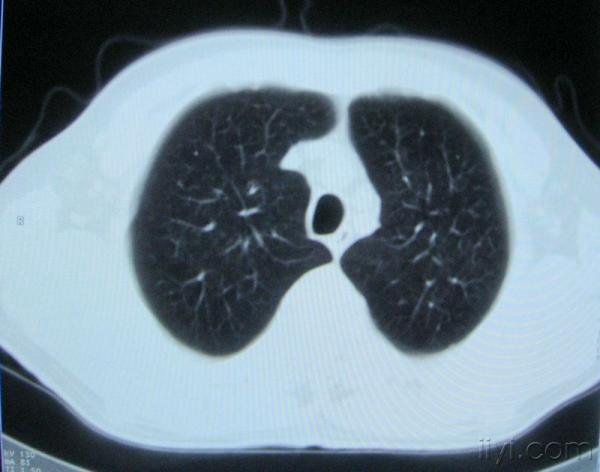

男。60岁,胸片示支气管炎治疗后复查CT。

你指那个肯定是淋巴结,中央系坏死,这很常见,特别在双侧腹股沟会经常看到。这个双侧腋窝及纵隔见多发小淋巴结征。

根据位置考虑应该是淋巴结,密度不均,是因为肿大的淋巴结中心液化坏死